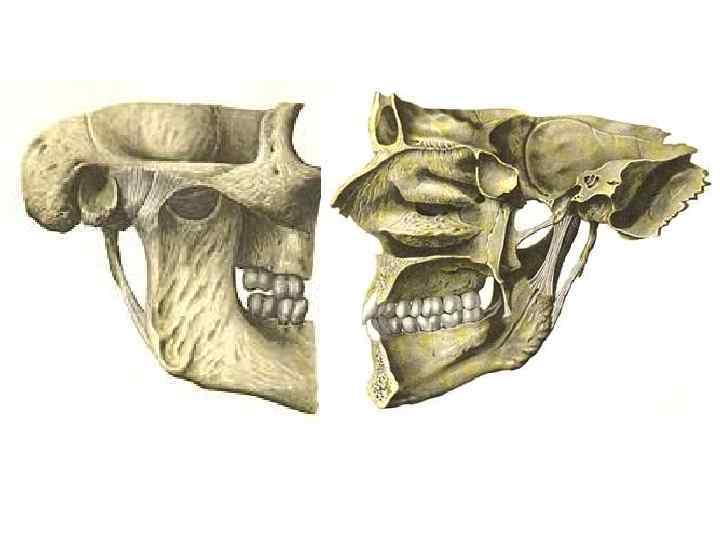

Верхня щелепа (maxilla)

Нижня щелепа (mandibula)

Лобова кістка (os frontale)

Скронева кістка (os temporale)

Клиноподібна кістка (os sphenoidale)

Велична кістка (os zygomaticus)

Решітчаста кістка (os ethmoidale)

Піднебінна кістка (os palatinum)

Нижня носова раковина (concha nasalis inferior)

Носова кістка (os nasale)

Сльозова кістка (os lacrimale)

Леміш (vomer)